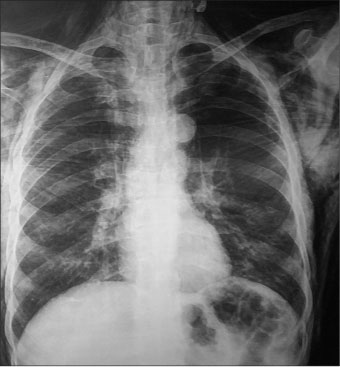

Two months after treatment completion (second follow-up), the patient presented with breathlessness. Chest X-ray (posteroanterior view) [Figure 1] and CT of the neck and chest showed extensive subcutaneous emphysema in the neck and axilla extending to the mediastinum [Figure 2]. He was referred to the chest unit where an intercostal drain (ICD) was inserted. The ICD relieved the pneumomediastinum and subcutaneous emphysema, and the patient was symptomatically better. After withdrawing the ICD, he was discharged from hospital. One week later, he died suddenly at home after an attack of coughing.

| Figure 1:A chest X-ray (posteroanterior view) showing subcutaneous emphysema in the neck

A chest X-ray usually detects pneumomediastinum and subcutaneous emphysema although better visualization is obtained through CT scan. In our case, CT scan showed extensive pneumomediastinum and subcutaneous emphysema. The patient underwent respiratory failure, which resulted in his death 2 months after the completion of treatment. The respiratory failure may have been chemotherapy drug induced or caused by forced expiration (e.g., the Valsalva maneuver with breath holding for a prolonged period).[2]